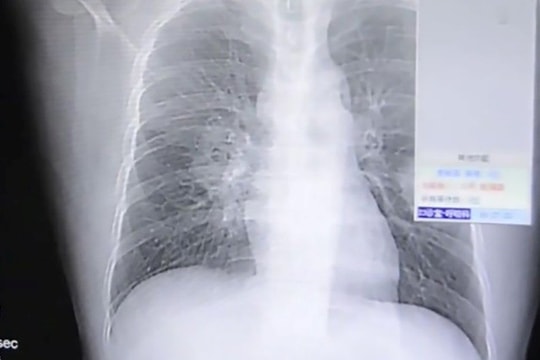

Khám lâm sàng ghi nhận vùng vai và cánh tay phải sưng đỏ, đau dữ dội. Kết quả siêu âm và chụp CT phát hiện viêm lan tỏa dưới da, kèm viêm bao hoạt dịch khớp vai. Không tìm thấy ổ nhiễm ở vị trí khác, các bác sĩ xác định vị trí tiêm tại phòng khám là đường vào duy nhất gây nhiễm trùng.